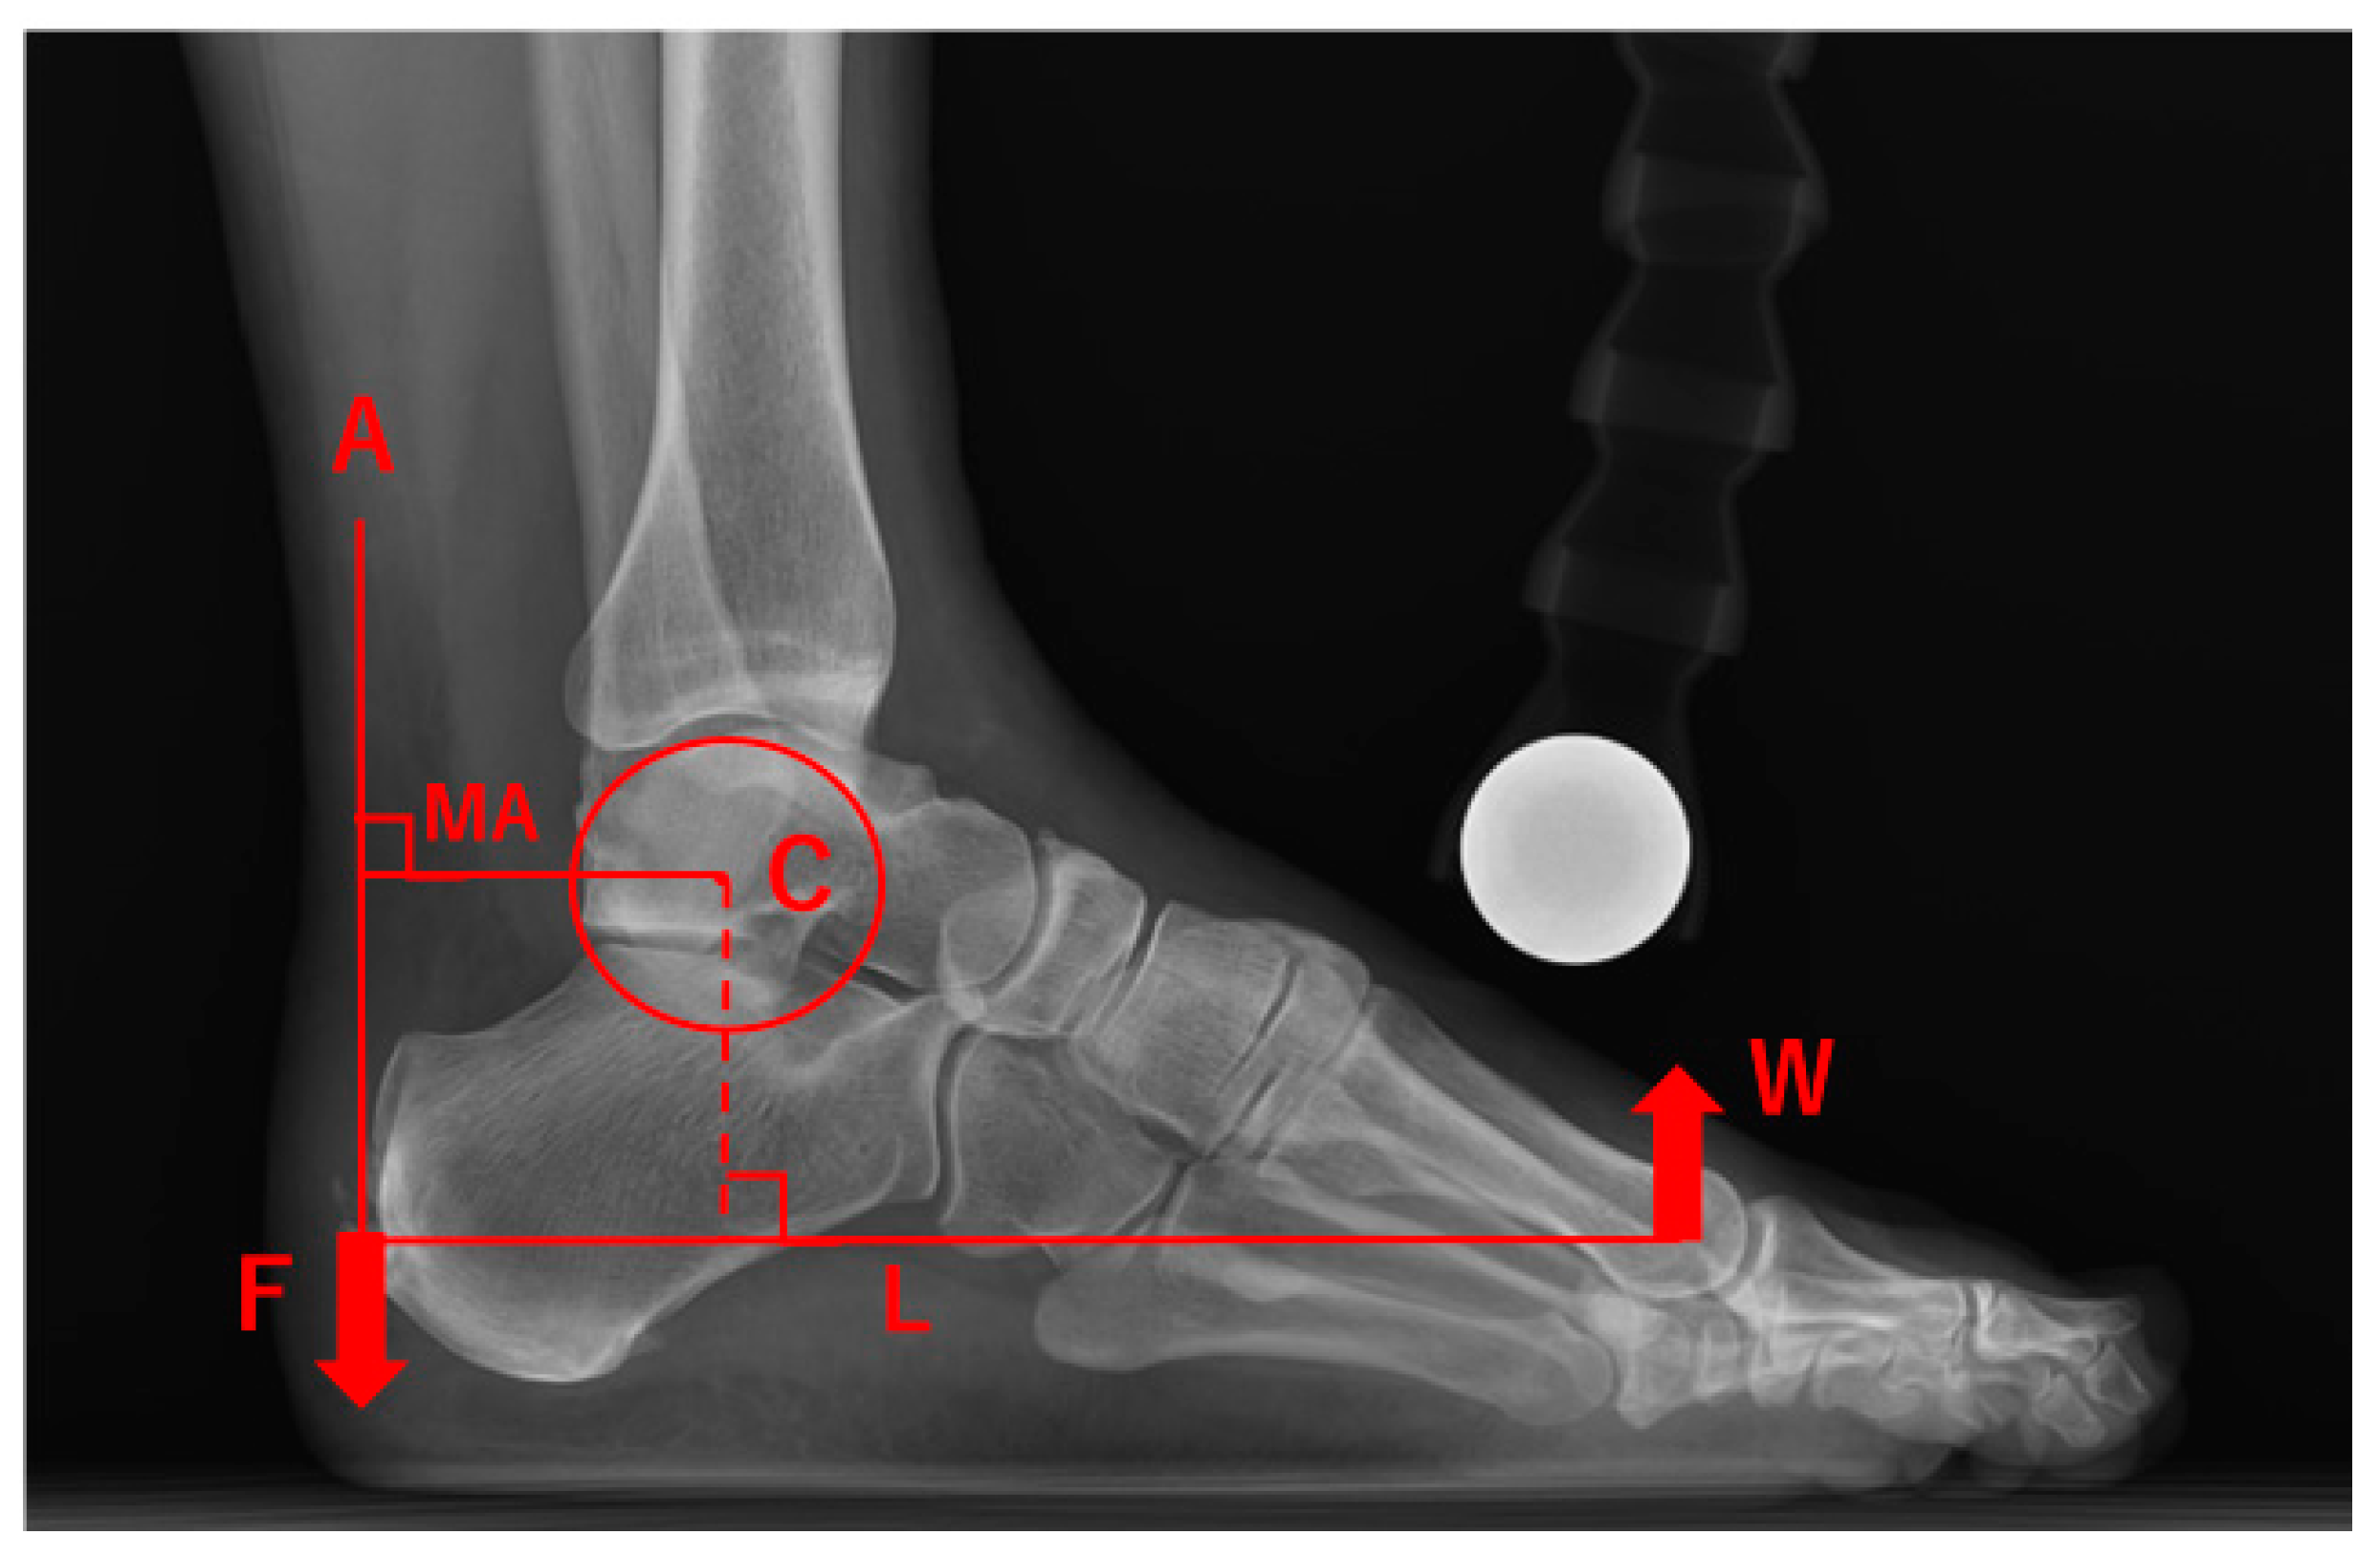

Effects of Achilles Tendon Moment Arm Length on Insertional Achilles Tendinopathy